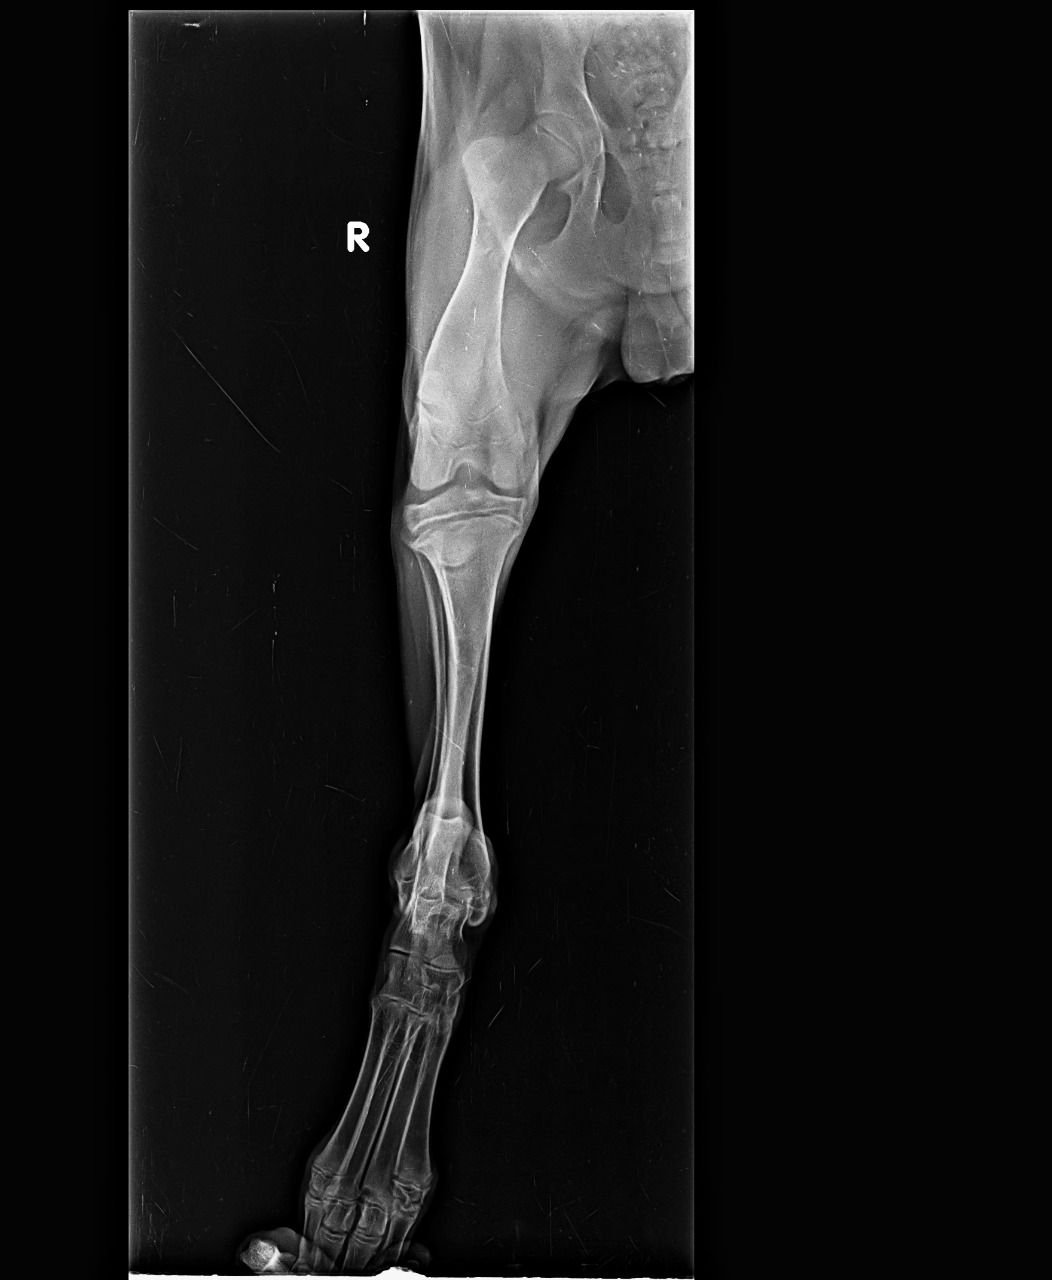

With a aim of “सर्वे भवन्तु सुखिनःI सर्वे सन्तु निरामया:I”, X RAY HOUSE, ANAND started Animal Imaging department for small animals.

We are pioneer of radio-diagnosis in small animals like dog, cat, rabbit, turtle etc. in Gujarat.